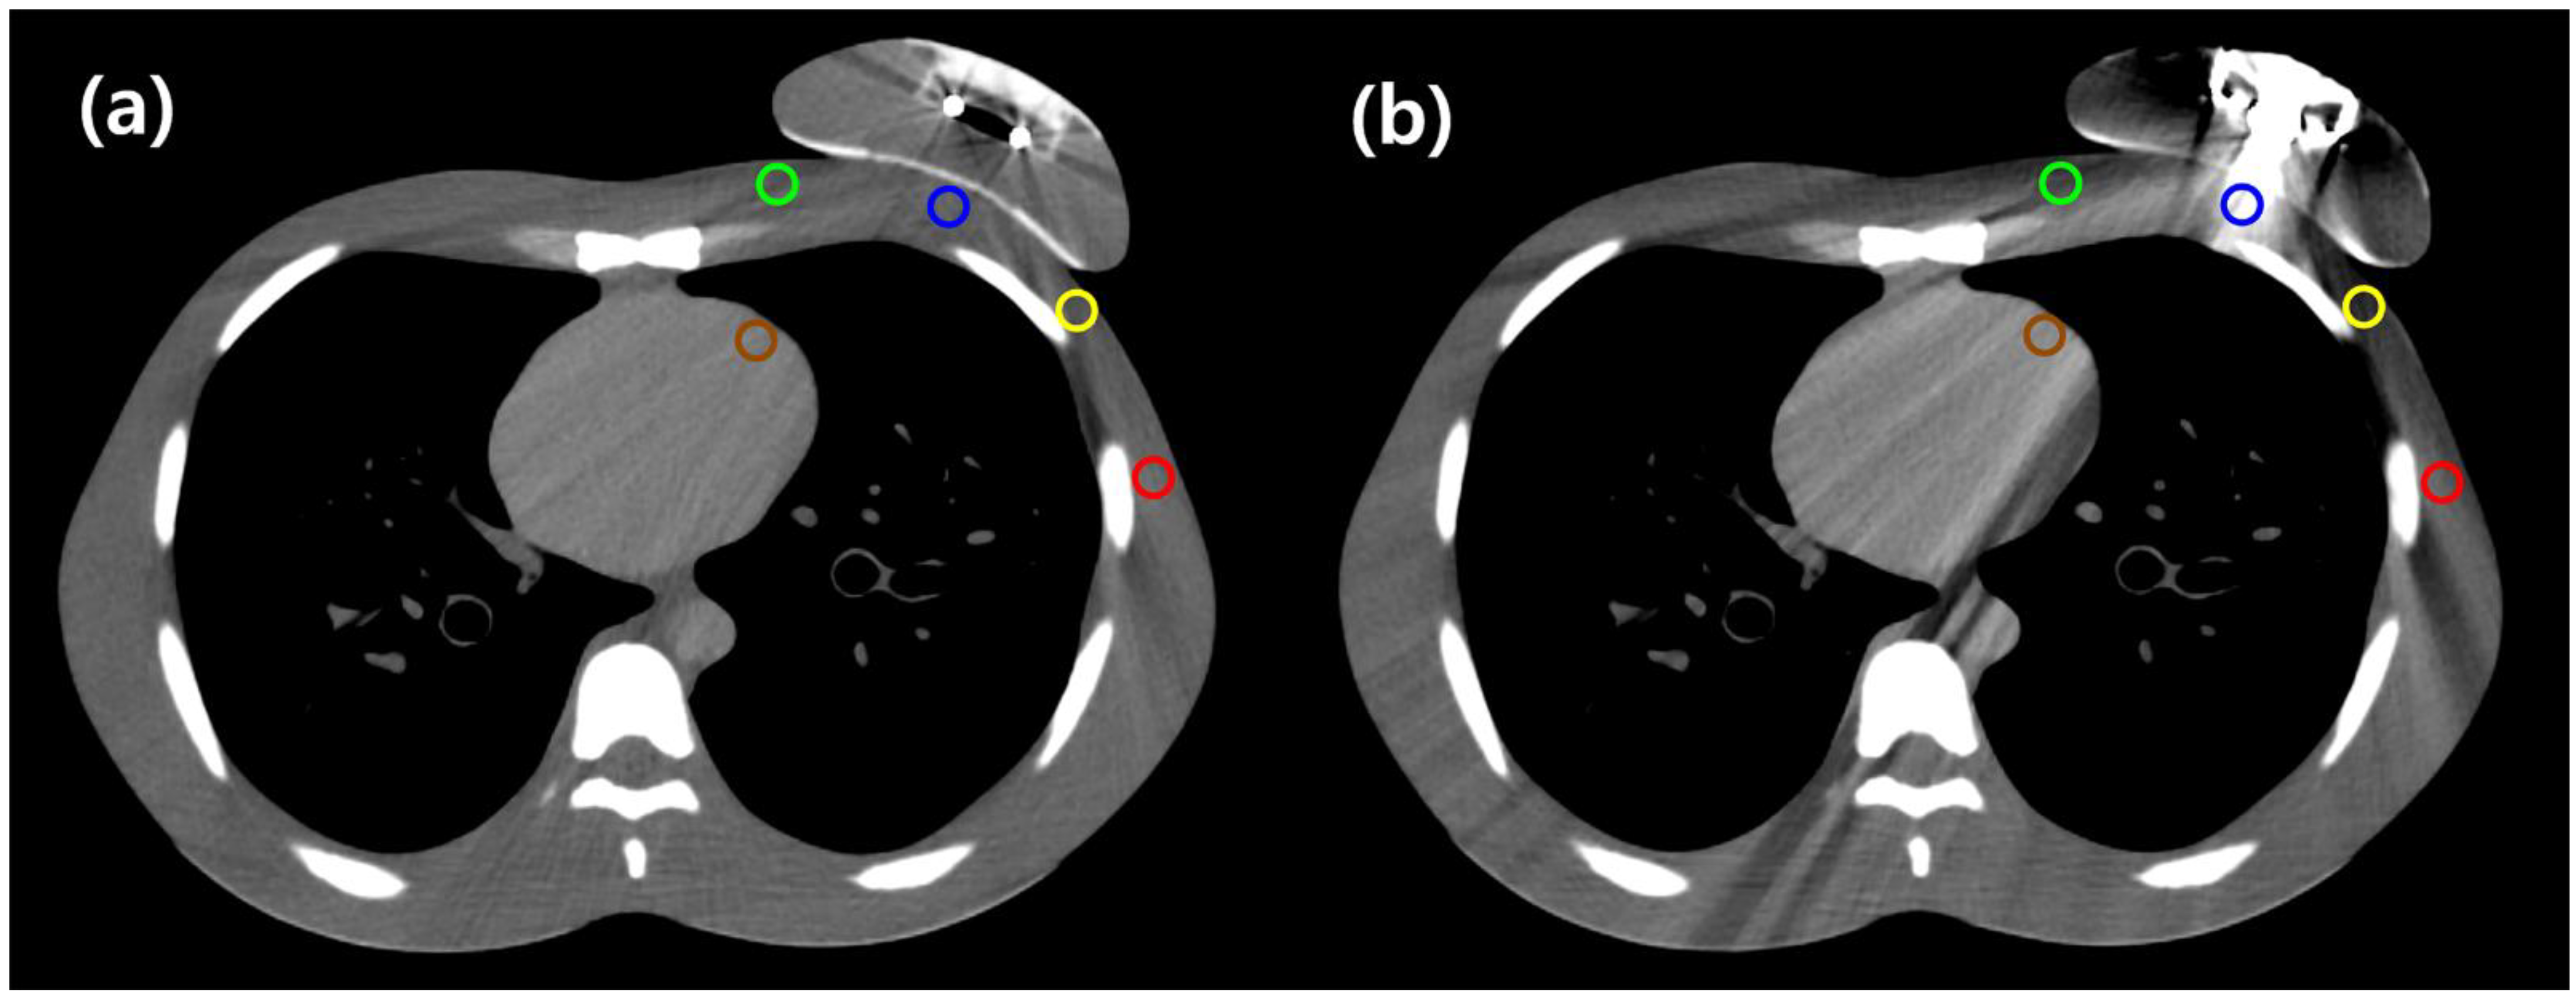

| Points of the Reference ROIs | RFID Port | Metallic Port | ||||

|---|---|---|---|---|---|---|

| Averaged HU | Averaged HU Difference | p-Value | Averaged HU | Averaged HU Difference | p-Value | |

| A (central chest wall) | −2.73 | −18.33 | 0.043 | 118.57 | −139.63 | 0.007 |

| B (medial chest wall) | −19.36 | 8.17 | 0.028 | −34.62 | 23.43 | 0.017 |

| C (lateral chest wall) | −37.36 | 14.93 | 0.028 | −74.37 | 51.94 | 0.005 |

| D (axilla) | −0.92 | −15.14 | 0.005 | −12.32 | −3.74 | 0.169 |

| E (left anterior descending artery) | 32.41 | −2.86 | 0.059 | 44.71 | −15.16 | 0.005 |